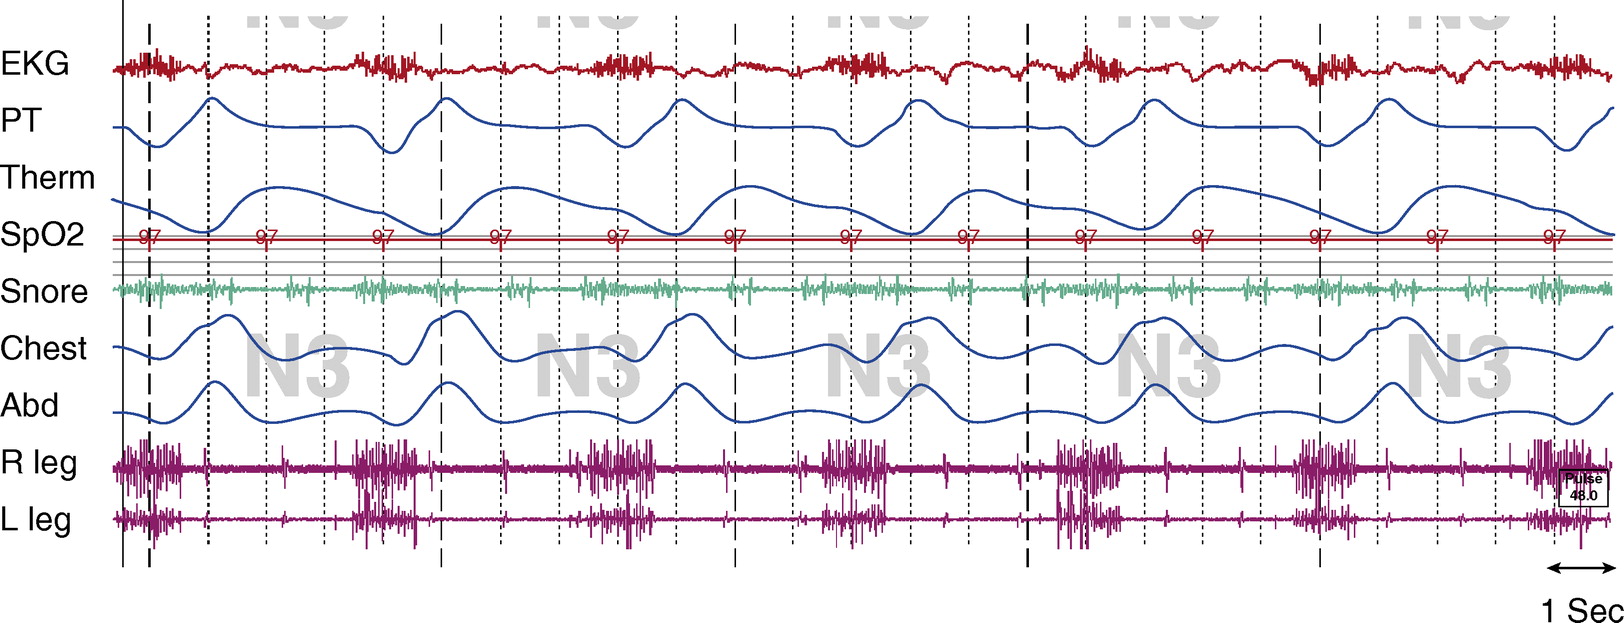

Figure 2.

Stage N3, tracheostomy open.Tcco2 was 40 to 45 mm Hg throughout study. Chest and Abd = piezo-electric respiratory belts for chest and abdomen, respectively; EKG = electrocardiogram; PT = pressure transducer; R leg and L leg = electromyogram of right leg and left leg, respectively; Spo2 = pulse oximetry–determined oxygen saturation; Tcco2 = transcutaneous CO2; Therm = thermistor.